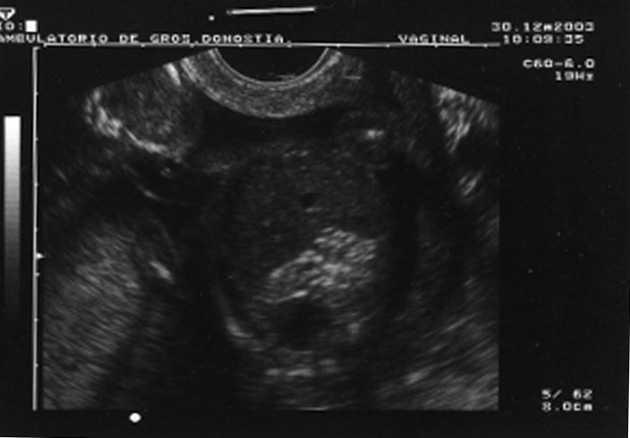

Al cabo de una semana se repite la ecografía, con los siguientes hallazgos: frecuencia cardíaca fetal (FCF) positiva; feto en posición cefálica; sexo masculino. peso fetal en percentil 10-25; aumento generalizado del espacio subaracnoideo, con aspecto de parénquima encefálico de pequeño tamaño y con escasas circunvoluciones; se observa comunicación entre las astas anteriores de los ventrículos laterales; cerebelo de morfología anómala con ausencia parcial de vérmix cerebeloso y cisterna magna límite; notable hiperecogenicidad intestinal; líquido amniótico normal. El diagnóstico fue: variante de Dandy-Walker + aumento de espacio subaracnoideo + holoprosencefalia lobar + hiperrefringencia intestinal (figs. 1 y 2).

-- Holoprosencefalia lobar: el hallazgo que sugirió la holoprosencefalia lobar fue la comunicación entre las astas anteriores de los ventrículos laterales. El aspecto del parénquima encefálico de pequeño tamaño, con escasas circunvoluciones, y el aumento del espacio subaracnoideo apoyaban dicho diagnóstico.